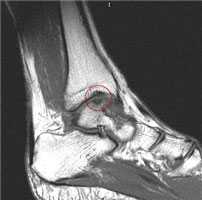

На МРТ выявляется рассекающий остеохондрит с отделением костно-хрящевого фрагмента от таранной кости.

МРТ является ценным инструментом в комплексе диагностики ОХПТК для оценки отека костной ткани, а также выявления скрытых повреждений субхондральной кости и хрящевого покрытия, которые могут быть пропущены при стандартных рентгенограммах или даже КТ. МРТ - самый лучший инструмент оценки для определения стабильности и жизнеспособности фрагмента таранной кости при его отслоении и эта информация может быть решающей в тактике выбора того или иного метода хирургического лечения. Однако, для определения размеров отслоившегося фрагмента таранной кости наилучший метод КТ, так как данные размеров по МРТ могут не соответствовать действительности в сторону переоценки последних. Hepple с соавторами изучив многочисленные данные МРТ диагностики разработали систему классификации ОХПТК на основе этого метода (Табл. 2) [23]. Однако, наиболее широко принятая система классификации, основанная на КТ-это классификация Ferkel и Sgalione (Табл. 3; Рисунок 4) [24]. Классифицировать ОХПТК также возможно выполнить интраоперационно, на основе артроскопических данных о состоянии остеохондрального поражения. Наиболее широко используется система Ferkel/Cheng (Табл. 4) [25], эта система классификации, в отличие от обычных рентгенограмм, КТ и МРТ, лучше всего взаимосвязана с исходами лечения пациентов.

В результате механического повреждения либо окклюзии артерий развивается ишемия костной ткани, что приводит к образованию участка некроза. Ответной реакцией на сформировавшуюся зону некроза являются процессы реоссификации, реваскуляризации и резорбции некротической ткани. В начале заболевания плотность здоровой и некротической костной ткани одинаковая, поэтому рентгенологически зона некроза не выявляется [8]. На данном этапе МР диагностика является более чувствительным методом выявления асептического некроза, когда рентгенологическая картина еще нормальная (рисунок 1). С течением времени, по мере того, как происходит резорбция костной ткани вокруг зоны некроза, возникает разница в плотности здоровой и некротической костной ткани. Некротическая ткань не подвергается резорбции, т.к. лишена притока крови. На данном этапе изменения происходящие в таранной кости проявляются рентгенологически. Зона асептического некроза выглядит как участок уплотнения (склероза) костной ткани.